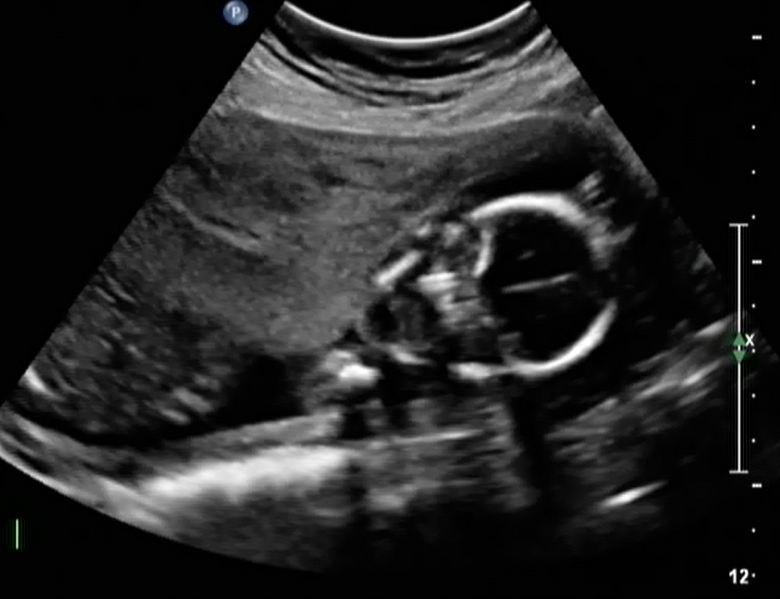

It took nearly two years of treatment, but Linda eventually got pregnant. She wanted to keep it a secret until she reached her second trimester but unfortunately, she never made it. she didn’t want to try again. But then, she changed her mind.